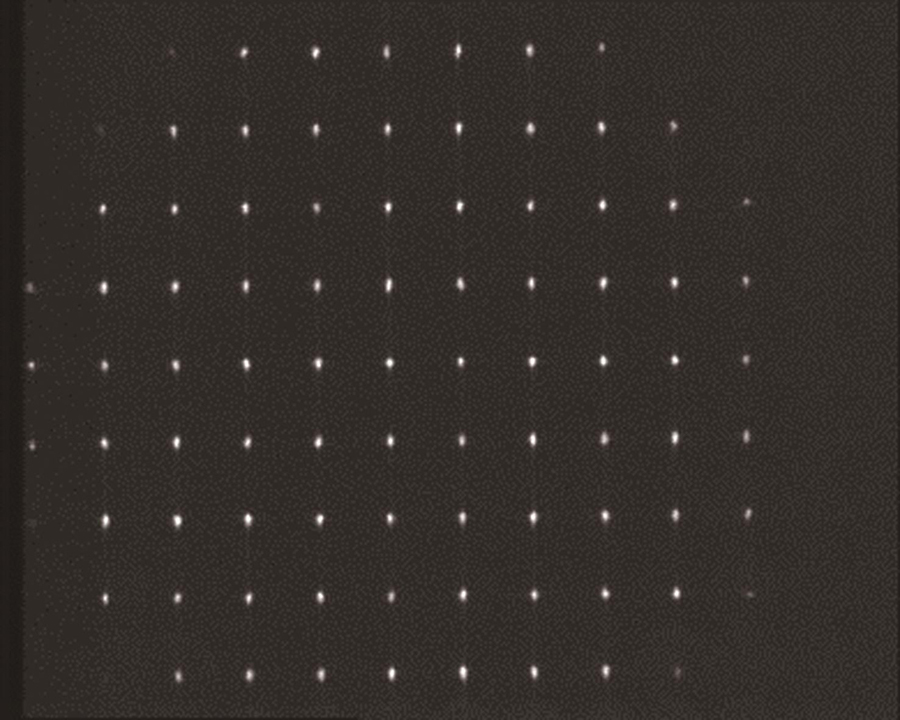

Five volunteers were recruited inside the laboratory, and the operator measured the subject’s left eye using the system experimental prototype and randomly showed the result of the eye axis length, radius of curvature, anterior chamber depth, and images of the measured human eye on the wavefront aberration sensor (Fig.3, Fig.4, Fig.5, Fig.6). The quality of the acquired images was good. The experimental prototype was used to measure the standard eye model with different diopters. The results of the single-sample t-test showed that the significance of the P value was greater than 0.05 (Table 1), and there was no difference between the diopter detection value of the experimental prototype and the standard value of the standard eye model, indicating that the experimental prototype could ensure measurement accuracy. From the values of Sw and TRT, it can be deduced that both the ocular biological parameters and diopter measurements have high repeatability. The CoV of eye biological parameters was less than 3%, the variation in the axial length and corneal curvature was smaller (CoV is less than 0.256%), and the ICC was higher than 0.6, reflecting high consistency (Table 2). The Bland-Altman analysis of the eye axis length, radius of curvature, and anterior chamber depth measured by the experimental prototype and IOL Master 500 showed no significant difference (P>0.05); the difference range was very small, and the 95% consistency limit was -0.045-0.056 mm, -0.037-0.056 mm, -0.534-0.355 mm, respectively, and all the measurement results were within the consistency interval (Table 3).

2.5 屈光度测量光路设计

在本设计中,采用准直的SLD(S3)激光作为参考波前的光源,其由眼轴测量光路进入人眼,经眼底反射后携带人眼的光学波前,经BS2、BS1以及透镜L5和L6组成的望远系统进入夏克-哈特曼波前传感器。其中,透镜L5、L6组成的望远系统将眼底与传感器成像相面形成光学共轭结构。同时,LED光源S4照明视标P图后经L3、R1、L4、BS2、BS1进入人眼,通过视标P的运动来调节屈光度误差,配合夏克-哈特曼波前传感器实现人眼波前的图像采集。通过图像处理计算出透镜阵列光斑的移动量,使用最小二乘法进行波前重建。波前像差使用7阶36项Zernike多项式展开,根据Zernike系数与球镜度、柱镜度的关系计算临床上的球差、散光及散光轴位数值[20]。

在实验室内招募了5名志愿者,因为都是年轻人群,因此没有设置排除条件。虽然这5名志愿者的眼球有不同的屈光状态,但基本都是健康的。采用本团队搭建的实验样机对5位受试者的左眼进行测量,采集的典型结果如

1)硬件方面。本次实验使用的基于夏克-哈特曼传感器的测量系统有动态范围、灵敏度、探测精度等指标,可从微透镜阵列尺寸、CCD尺寸、CCD分辨率和透镜焦距这几个参数中选择适合人眼屈光度测量的最优参数。

2)算法方面。基于夏克-哈特曼传感器的测量技术测量屈光度的主要步骤是图像预处理、质心计算、斜率计算、波前重构、屈光度计算,而基于夏克-哈特曼传感器的人眼像差检测算法的精度取决于波前重构的精度,由波前重构理论可知光斑阵列的质心探测精度决定了波前重构的精度。因此可以从质心计算入手,提出新算法或改进相关算法,进一步提高屈光度测量的重复精度。